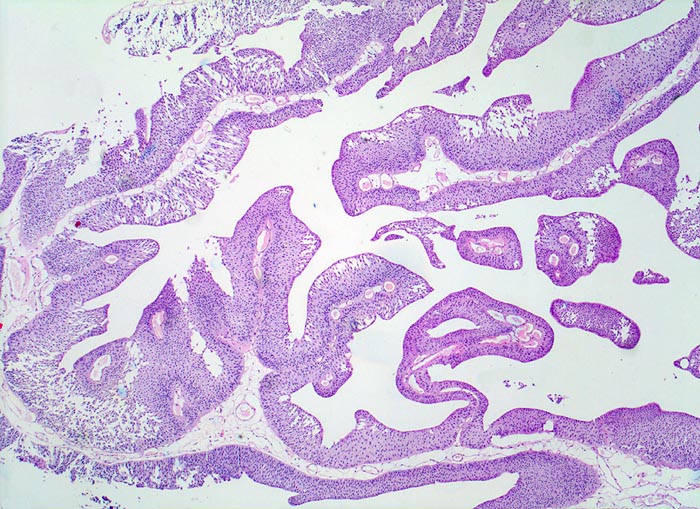

Nicht invasives papilläres Urothelkarzinom pTa

Harnblase

Lockeres fibrovaskuläres Stroma wird bedeckt von einem verbreiterten Urothel. Eine durchgehende Basalmembran ist erkennbar. Das Stroma wird nicht infiltriert.

Die zystoskopische Abklärung einer Makrohämaturie ergab einen papillären Tumor an der Blasenhinterwand. Der Tumor wird transurethral reseziert.

pTa Tumoren stellen nicht invasive Tumoren dar. Trotzdem werden sie in der WHO Klassifikation als papilläre Karzinome bezeichnet (der Begriff Karzinom sonst ausschliesslich auf invasive epitheliale Tumoren mit metastatischer Potenz angewendet).